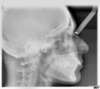

Radios pendant le traitement